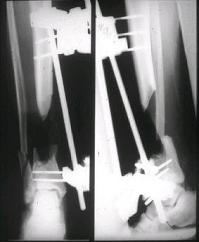

аппаратом постепенно создана рекурвация для сближения контактов мышц (сухожилий) передней группы голени. #5;#6. Наложен шов на сухожлилия М.

Tibialis anterior и M extensor digitorum L. Одновременно компактотомия костей голени в В/3 для замешение дефекта костей. #7;#8. Постепенно